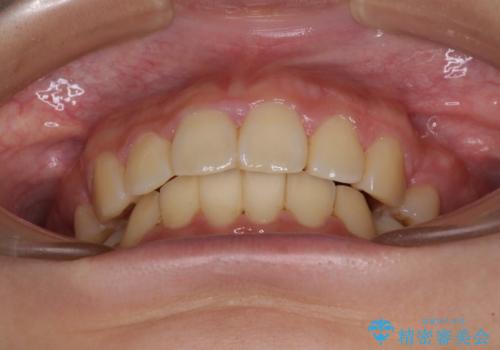

- 上下前歯を部分矯正したところ出っ歯になってしまったとのことで来院された患者様です。

上下左右第一小臼歯4本を抜歯して、積極的に口元を引っ込めるよう、ワイヤー装置にて矯正治療を行うこととしました。

治療後には口が閉じやすくなり、患者様には大変満足していただきました。